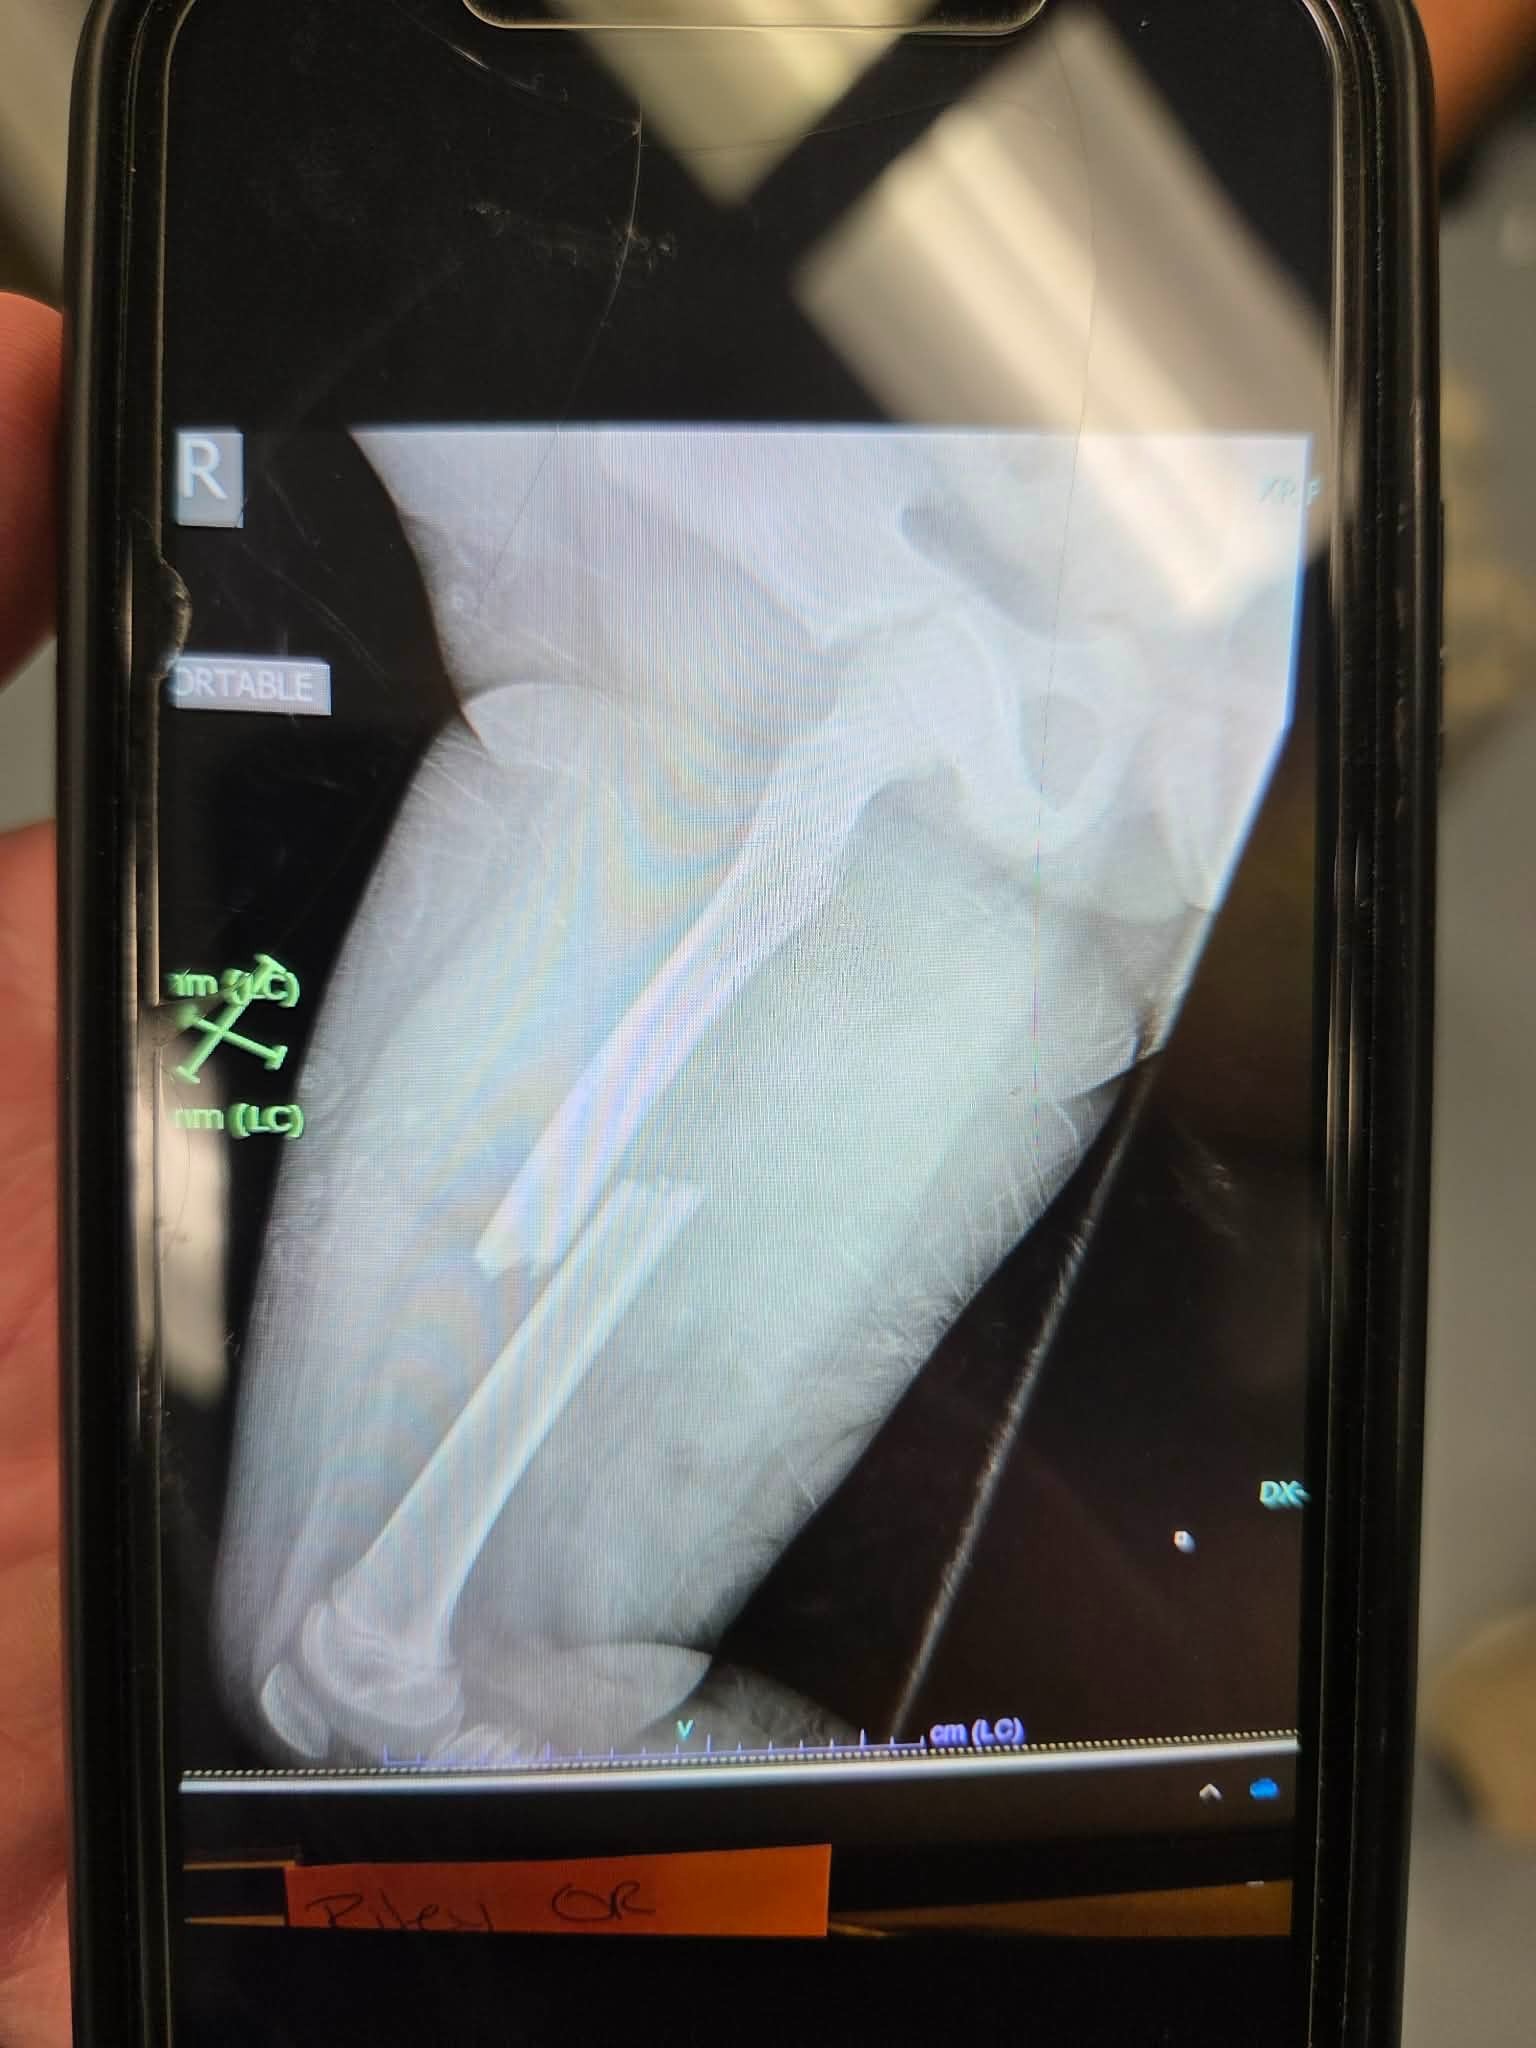

Carrie sustained multiple injuries, including two broken legs in multiple places as well as a broken ankle and kneecap, a laceration on her forehead that required several stitches, and a broken right arm.

Her fiancé suffered a broken femur, a broken ankle, and some minor spinal injuries.

Their 9-year-old daughter experienced a broken femur which required a rod and screws, as well as a fracture to her C11 vertebra, which required spinal surgery and the placement of rods and screws. She will also require a back brace for continued support. Also, due to the seatbelt she sustained injuries to her lower right abdomen. Those injuries include a torn diaphragm muscle, which was required to be stitched back together and the removal of her right kidney.